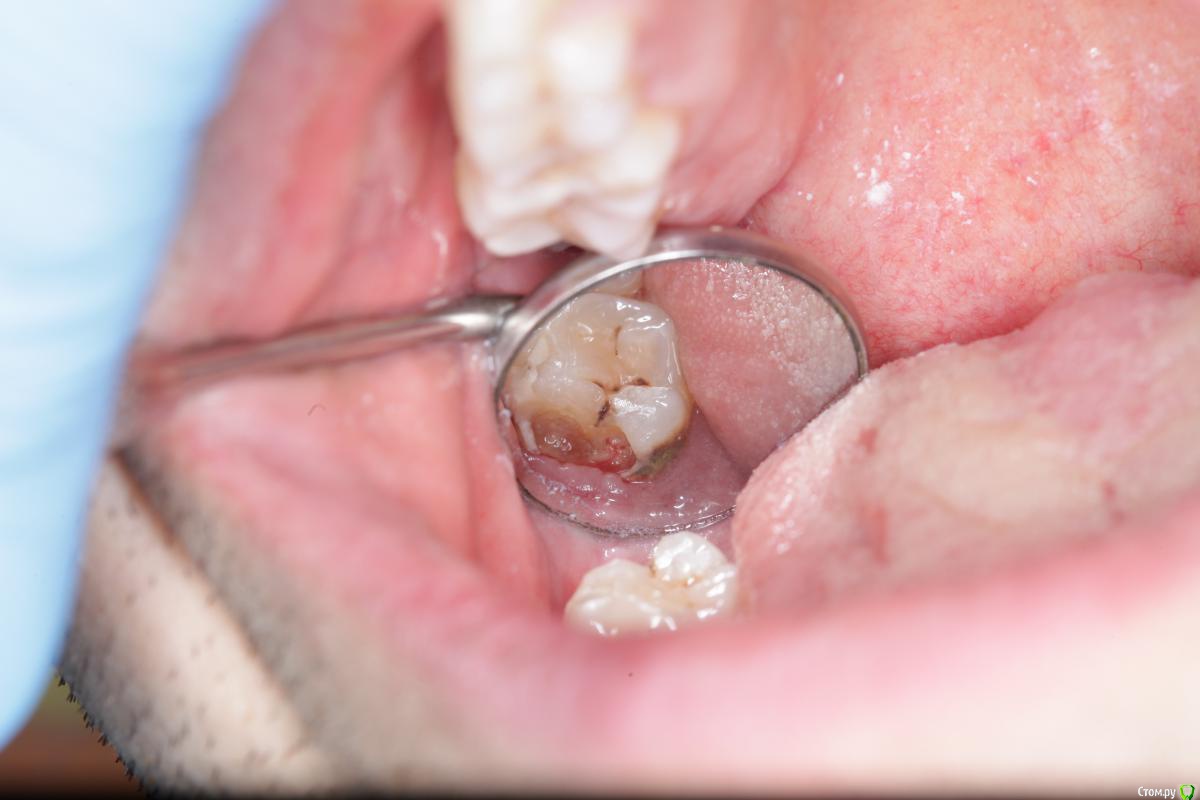

ger_berra Опубликовано 12 апреля, 2016 Поделиться Опубликовано 12 апреля, 2016 посмотрелIMG_6612.jpgСамые отвратные ,долгие и дешёвые работы! Фу! Ненавижу! И всегда бешусь,когда такое буээээээ приходит.У таких зубная щётка только для обуви! 1 1 Ссылка на комментарий